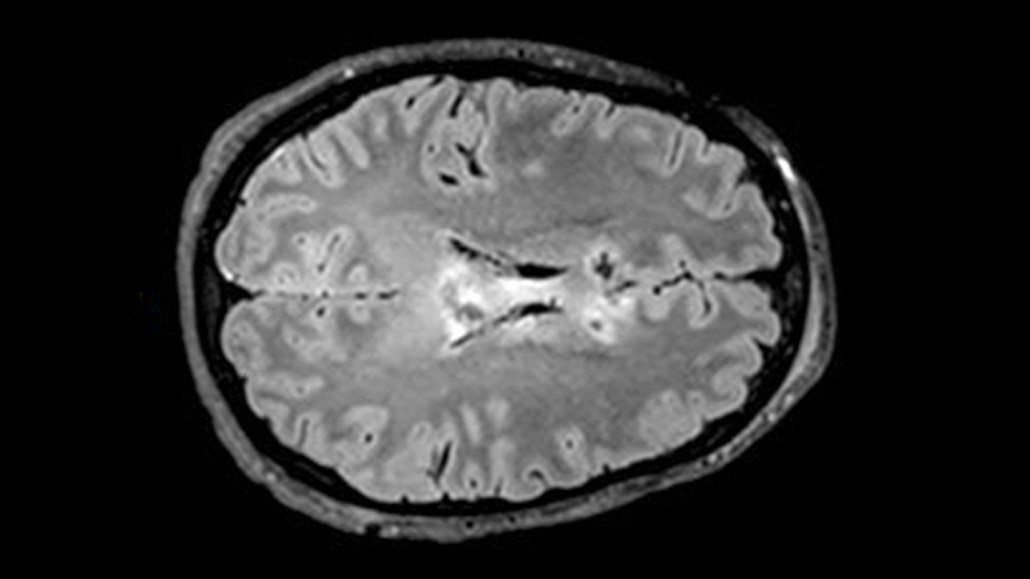

The fatty material surrounding fibers that send signals between neurons degenerates after a traumatic brain injury. A new study pinpoints a blood biomarker that can predict this damage.

Brain scans of 146 participants revealed that their peak NfL concentrations predicted the extent of brain shrinkage after six months, and axon damage at six and 12 months after injury, neurologist Neil Graham of Imperial College London and his colleagues found.